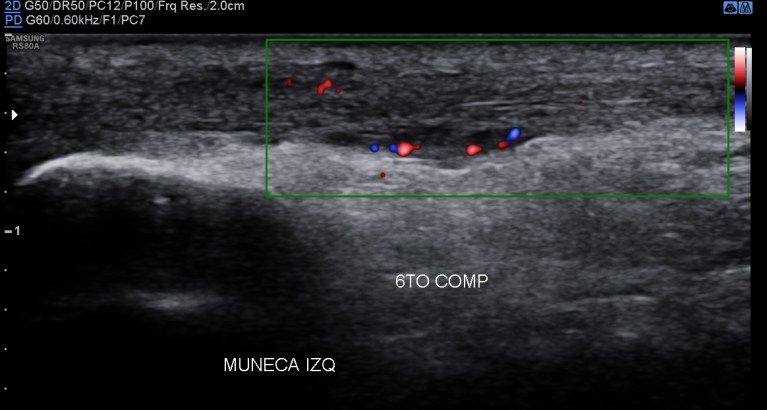

Situada en la corredera bicipital, vas a ver el bíceps como una estructura hiperecogénica, redondeada situado en el valle de la corredera. Observa como la imagen superior indica ausencia de líquido y normalidad y la inferior relación entre la anatomía y la patología donde el líquido rodea el tendón en relación con una posible tenosinovitis.